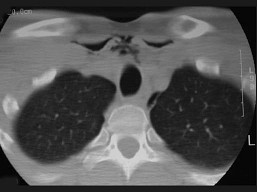

11.27歲男性,開車外出在高速行駛時翻車,呼吸困難,喉部腫脹,CT檢查如圖所示,請選擇正確的描述或診斷  (    )

正確答案:ABCE